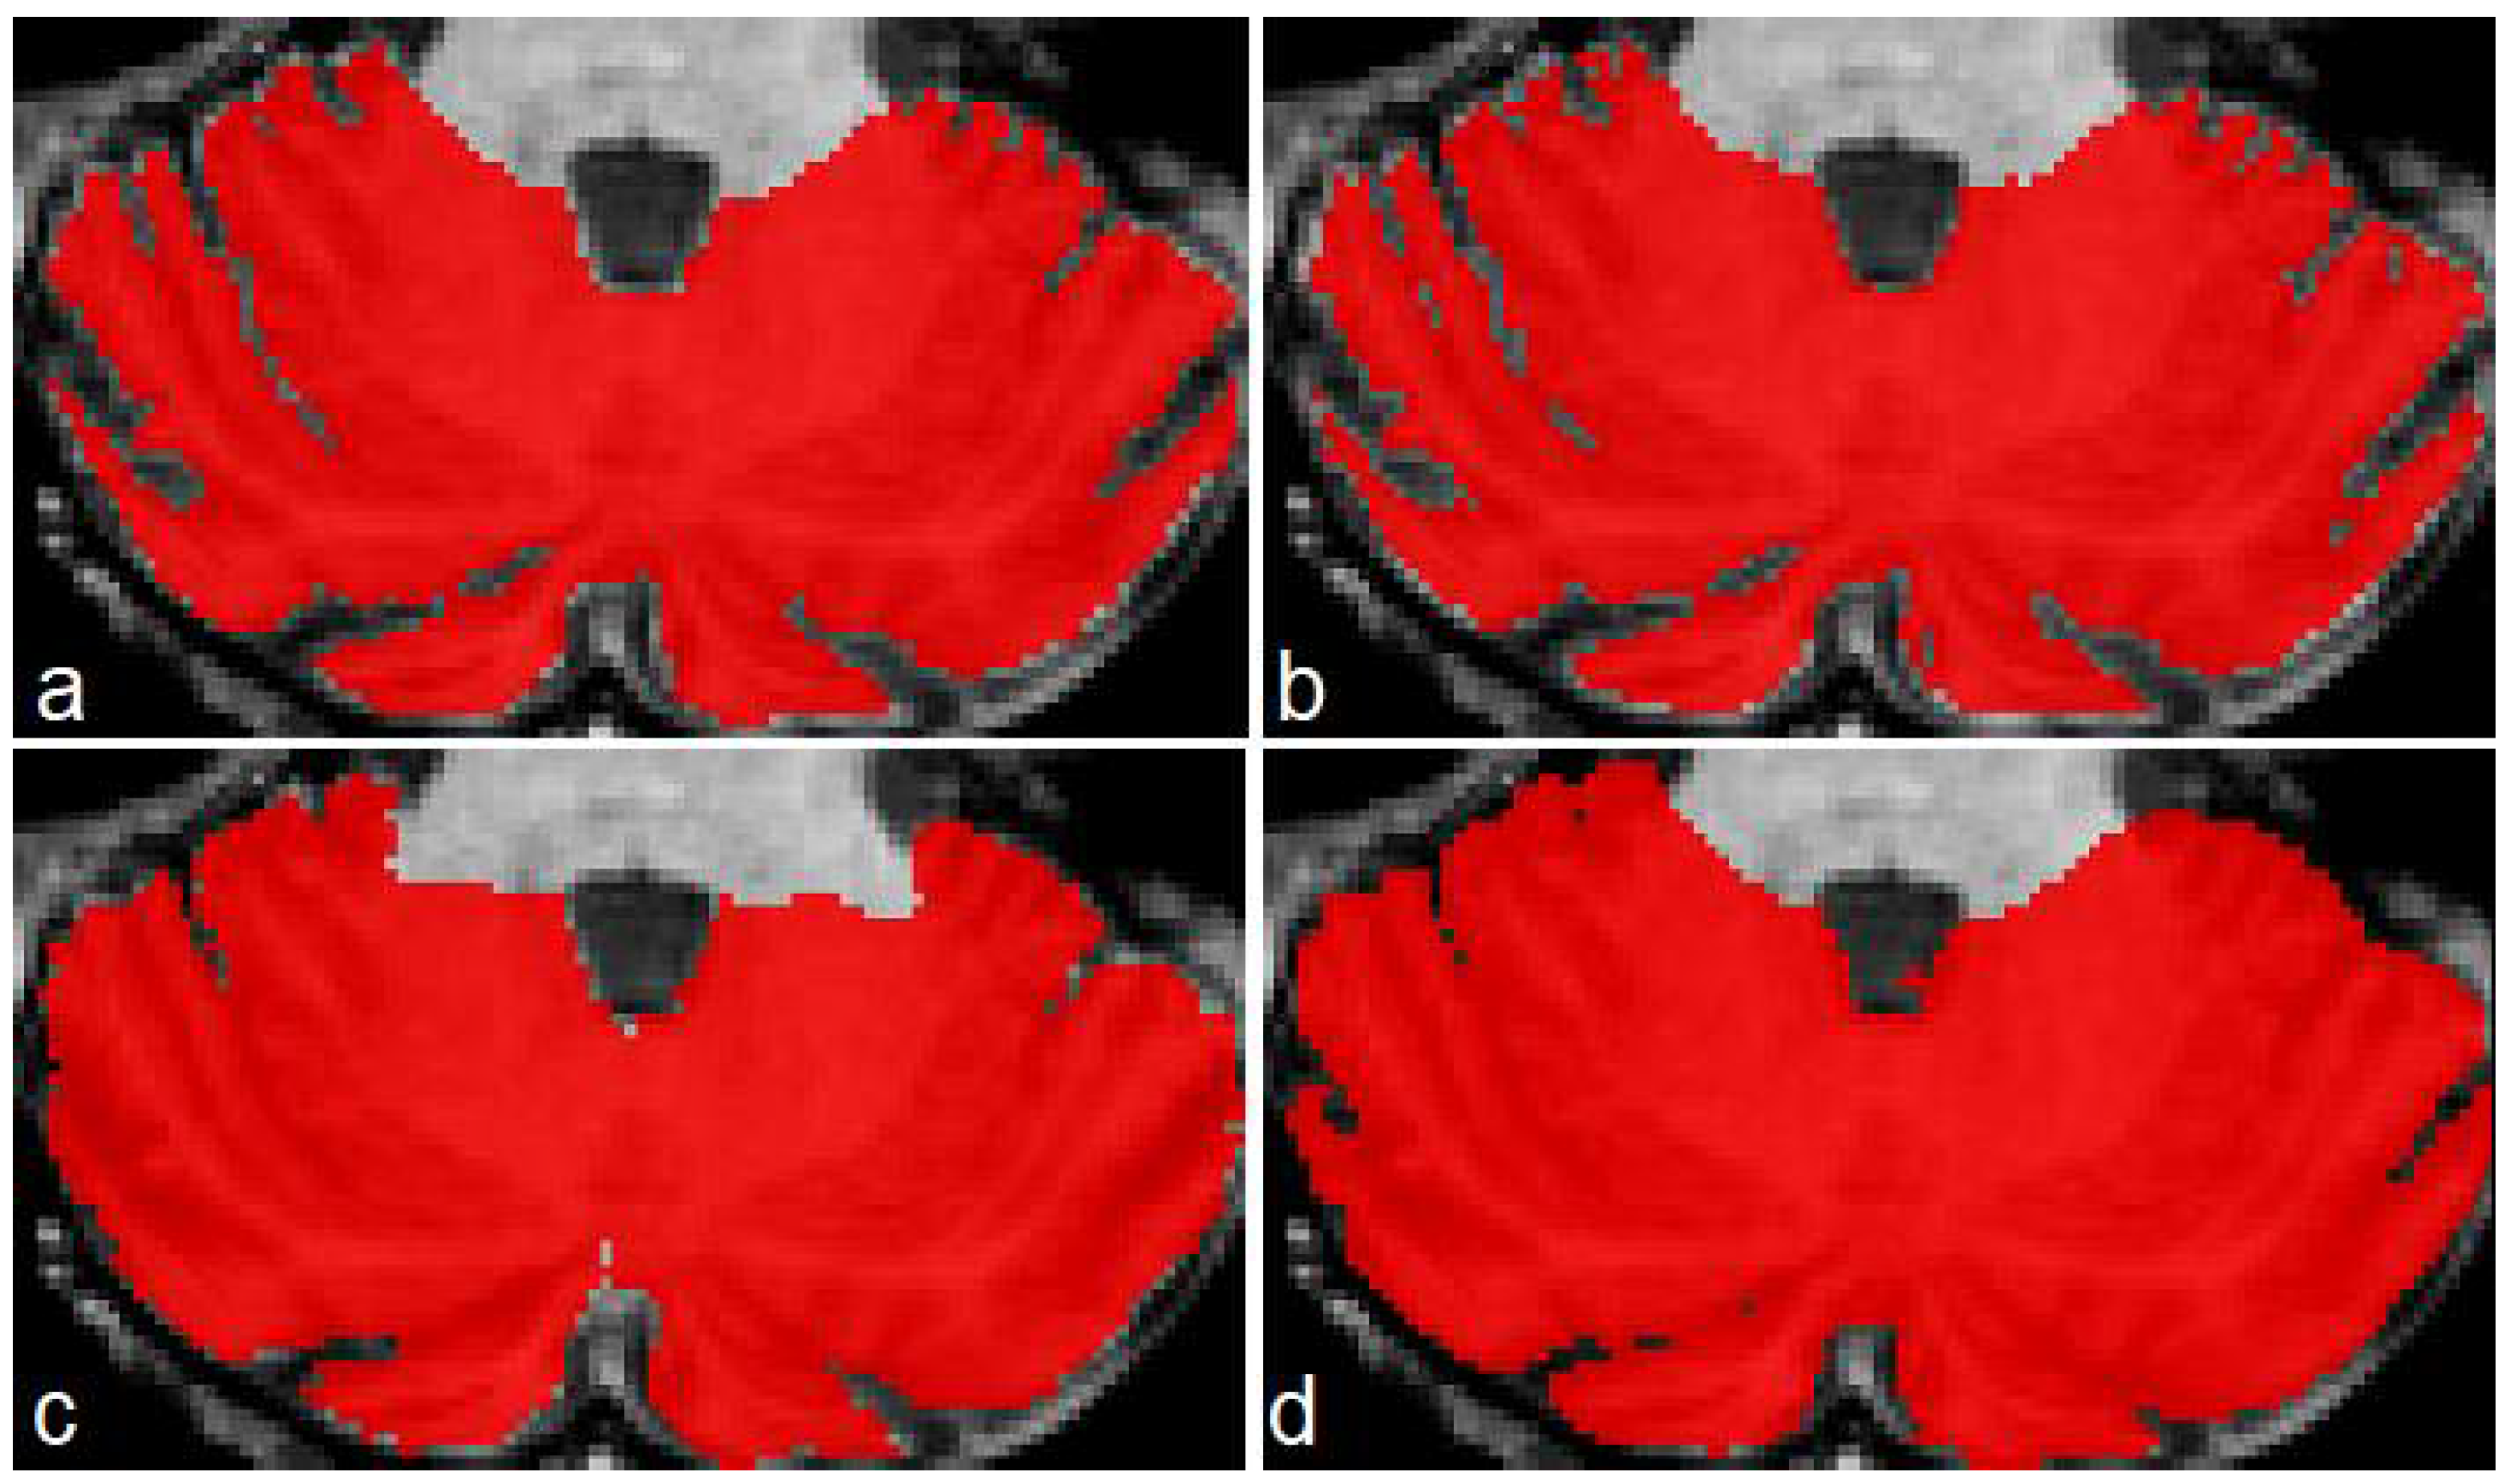

The three models (see Table 1) were tested on five unseen magnetic resonance images. The test subset contained one healthy control (subject 1), two presymptomatic carriers (subjects 2 and 4), and two SCA2 patients (subjects 3 and 5). Figure 4 shows a comparison between the original masks and the segmentations produced by M1, M2 and M3. It can be appreciated the similarity between original and segmented images. Some errors remain, mainly in the contour of segmented masks; those errors will be covered in next investigations. Table 3 shows the result of the evaluations on model M1, segmenting cerebellar fissures only.

Produced segmentations have relatively good scores. Mean DSC and OC are 0.854 and 0.898, respectively. All SP are above 0.99, which means an optimal recognition of background voxels. Low SN values represent some errors in the voxels belonging to cerebellar fissures, mainly in the MRI belonging to the healthy control (0.73, the minimum SN value). It seems that the best behavior was obtained for subject 3, one of the SCA2 patients in our dataset. Note that segmenting cerebellar fissures is a difficult task and, as such, characteristics change greatly between different people. Furthermore, no postprocessing was applied to the results of model M1. Figure 4d shows an example of the outputs produced by our model, compared against the ground truth mask in Figure 4a.

Table 4 shows the evaluation results for model M2 (segmentation of cerebellum tissue with its fissures). As observed, results for this model were much better than the previous one. This is a logical result, considering that segmenting a single, larger structure, which is always located in the same place on MRI, should be easier than segmenting smaller regions with many position changes. The best scores were achieved for the subject 4 MRI, producing better segmentations. The mean values for DSC and OC are 0.973 and 0.987, respectively. SP, SN and AUC are all above 0.98, which means a good background and foreground voxel classification. Figure 4e displays an example output from this model.

Table 5 shows the results for the model segmenting the whole cerebellum (M3). As in Table 4, all scores are above 0.95, which gives the idea of a high precision in the segmentation results. Mean DSC and OC are 0.969 and 0.982, respectively. As in evaluation for model M2, SP, SN and AUC are above 0.98, which means a high-quality segmentation. In a general way, the segmentations obtained by models M1, M2 and M3 have a good quality. Models M2 and M3 obtained better scores than M1.

Figure 4. Masks and predictions for an MRI belonging to one of the SCA2 patients in the test subset. The top row shows the original masks, obtained with the procedure described in Section 2.2, and the bottom row displays the segmentations produced by our models. Cerebellar fissures in (a,d), cerebellum tissue with fissures in (b,e), and whole cerebellum without any fissure in (c,f).